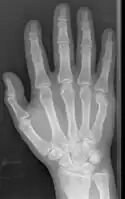

![]() | |

| Boxer's fracture of the 5th metacarpal head from punching a wall | |